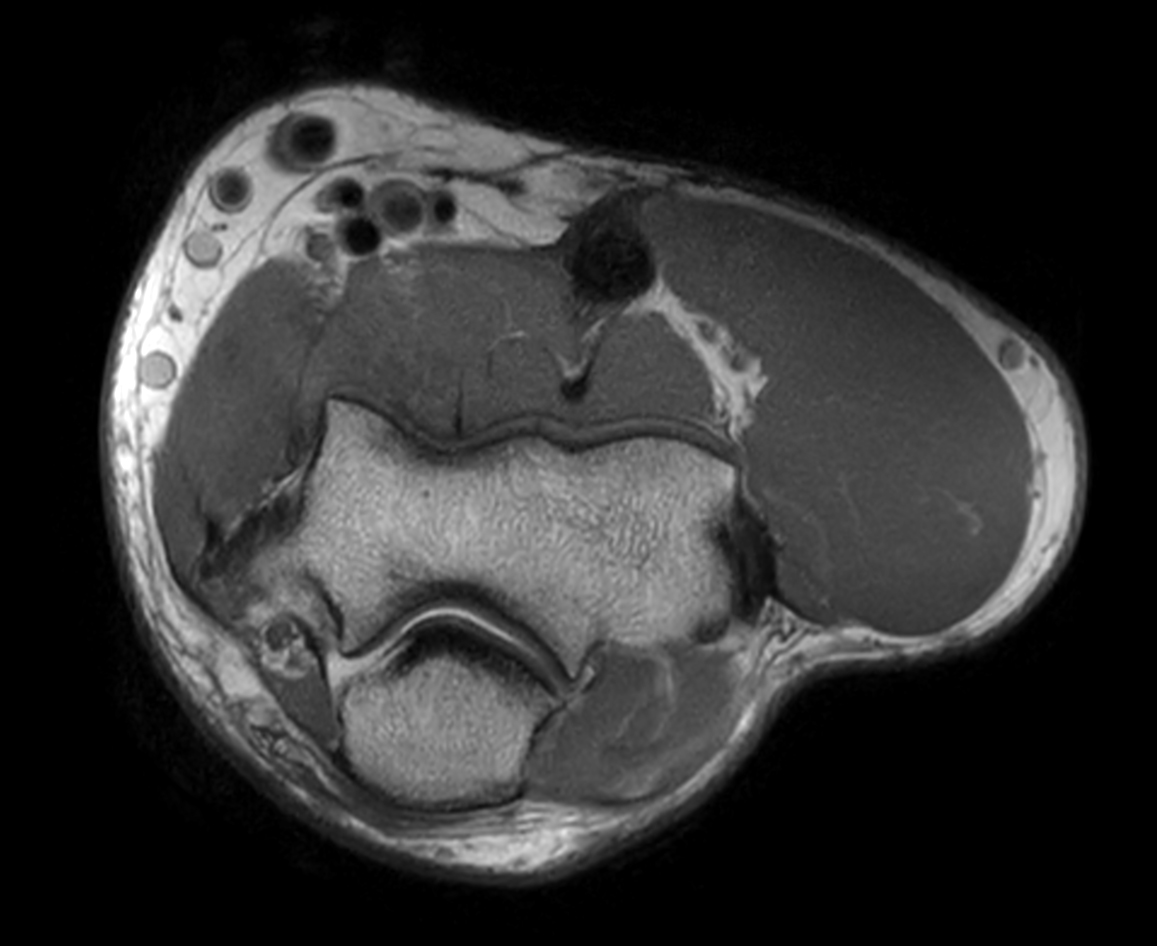

Axial T2w TSE